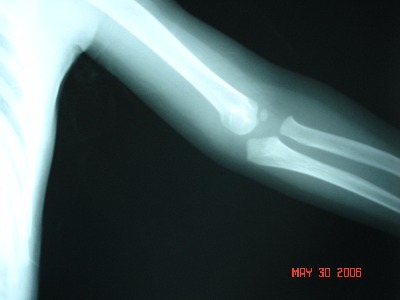

10月15日土曜日の午後で子供の肘が抜けて(肘内障:肘の脱臼)病院を探すのが大変ではないですか?

土曜日の午後6時まで診察していたので、受傷当日に受診でき、診断、治療(肘が抜けたのをその場で入れてくれた:整復してくれた)まで受けられてよかったです。と、感謝の言葉をいただきました(^^)

ふじた医院では土曜日の午後でも18時まで、整形外科はもちろんのこと、内科にも対応して診察しています。

交通事故による痛み、むちうちの症状、首の捻挫(頸椎捻挫、むちうち、首の痛み)、腰の捻挫(腰椎捻挫、腰の痛み)、けが、切り傷、打ち身(うちみ)、打撲、捻挫(ねんざ)、骨折、脱臼、やけど、肘が抜ける(肘内障)の後遺症で悩まれている患者様をトータルで治療し、保険(自賠責保険、労災保険等)にも対応している整形外科病院です。